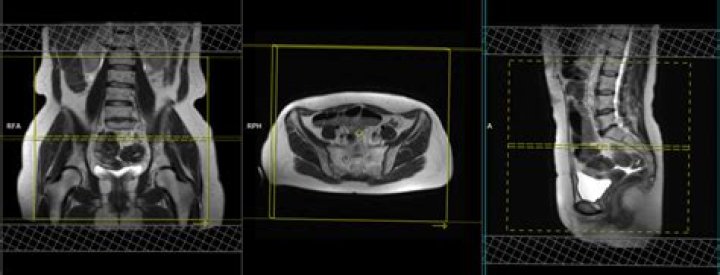

Can you see endometriosis on pelvic MRI?

Pelvic magnetic resonance imaging (MRI) is one imaging technique that doctors may use to help diagnose endometriosis. The test provides a picture of organs inside the pelvic cavity and shows endometrial growths that may require further investigation.

How does endometriosis appear on MRI?

On MRI, endometriomas present as solitary or multiple masses with a homogeneous hyperintense signal intensity on T1- and T1-fatsat sequences. The T1-fatsat helps differentiate endometriomas from mature cystic teratomas, which usually contain fat.

Currently, MRI is considered the best imaging technique for mapping endometriosis, since it provides a more reliable map of deep infiltrating endometriosis than physical examination and transvaginal ultrasound (TVUS) [8].